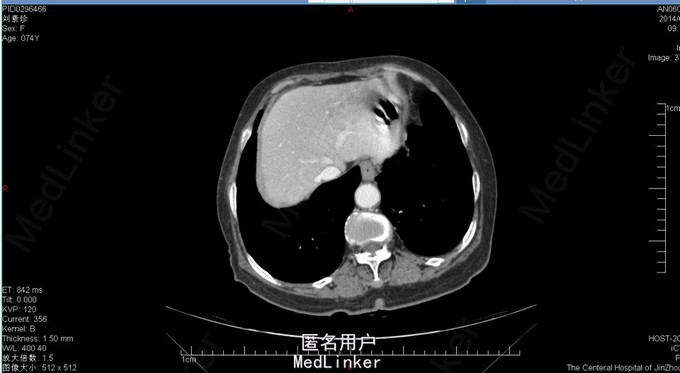

胆囊十二指肠瘘,结石性幽门梗阻

74岁女患,上腹部疼痛伴恶心呕吐3天。 3天前患者开始出现上腹部不适疼痛,同时伴有恶心、呕吐。呕吐物为胃内容物,餐后严重。患者在家自行消炎治疗,症状逐渐加重。患者为求进一步诊治来我院。 既往胆囊结石病史。

查体:上腹部压痛明显,伴反跳痛及肌紧张。 腹部ct:十二指肠内结石?(回忆部分)

胆囊十二指肠瘘,结石性幽门梗阻,腹膜炎。 给予患者胆囊切除+十二指肠修补局部引流?(记不太清)患者术后恢复还可以,顺利出院。

此病例为普外科轮转期间收集影像资料所得,病例内细致资料不全面,不能详尽分享。但此种病例少见,影像资料清晰,值得学习探讨。 欢迎普外专业同道探讨患者手术方式。让大家共同进步。